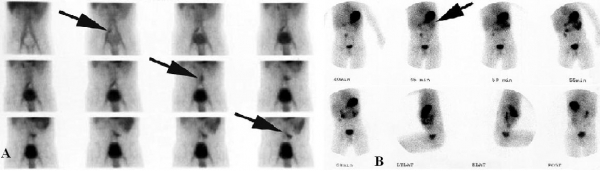

Chất đồng vị Tc-99m tập trung nhiều ở tế bào chế tiết chất nhầy niêm mạc dạ dày, nên dùng để khảo sát túi thừa Meckel chứa niêm mạc dạ dày lạc chỗ cho độ đặc hiệu cao. Ở trẻ em độ nhạy 85%, độ đặc hiệu 95%. Ở người lớn độ nhạy thấp hơn 63%, độ đặc hiệu 2%2. Những nguyên nhân làm cho dương tính giả: nang đôi dạ dày hoặc ruột non, lạc chỗ niêm mạc dạ dày vào ruột non bình thường, những nguyên nhân gây tăng sinh mạch máu ruột non như viêm loét (loét đại tràng, Crohn, …). Những nguyên nhân làm cho âm tính giả: túi thừa Meckel không chứa hoặc chứa quá ít niêm mạc dạ dày khiến không đủ độ tập trung của anion Tc-99m pertechnetate.

Hình 10: Túi thừa Meckel chụp nhấp đồ với đồng vị phóng xạ Tc-99m pertechnetate

A, ở bệnh nhân nam 17 tuổi, hình ảnh túi thừa Meckel là bóng tròn nhỏ từ từ hiện rõ qua theo thời gian chụp (mũi tên). B, bệnh nhân 4 tuổi, túi thừa Meckel bắt đầu hiện rõ ở 45 phút sau tiêm ( mũi tên). (Angela D. Levy, Christine M. Hobbs (2004). Meckel Diverticulum: Radiologic Features with

Pathologic Correlation. RadioGraphics; 24:576)